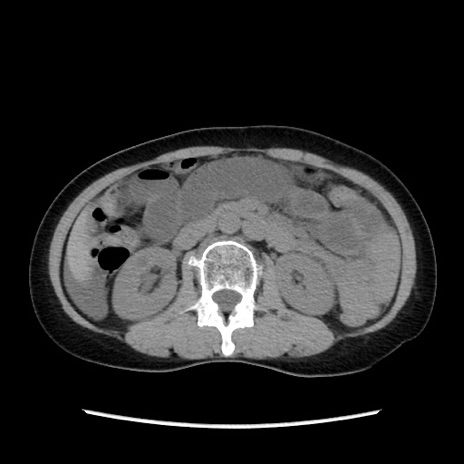

症例32(横断像)

【症例】40歳代 女性

【主訴】上腹部痛、嘔気・嘔吐

【現病歴】約9時間前頃から急に上腹部痛、嘔気、嘔吐が出現。改善しないため救急要請。

【既往歴】子宮頚癌(広汎子宮全摘術、放射線療法)、腸閉塞

【身体所見】腹部:平坦、軟、腸雑音亢進、上腹部を中心に腹部全体に圧痛あり。

【データ】WBC 8400、CRP 0.03